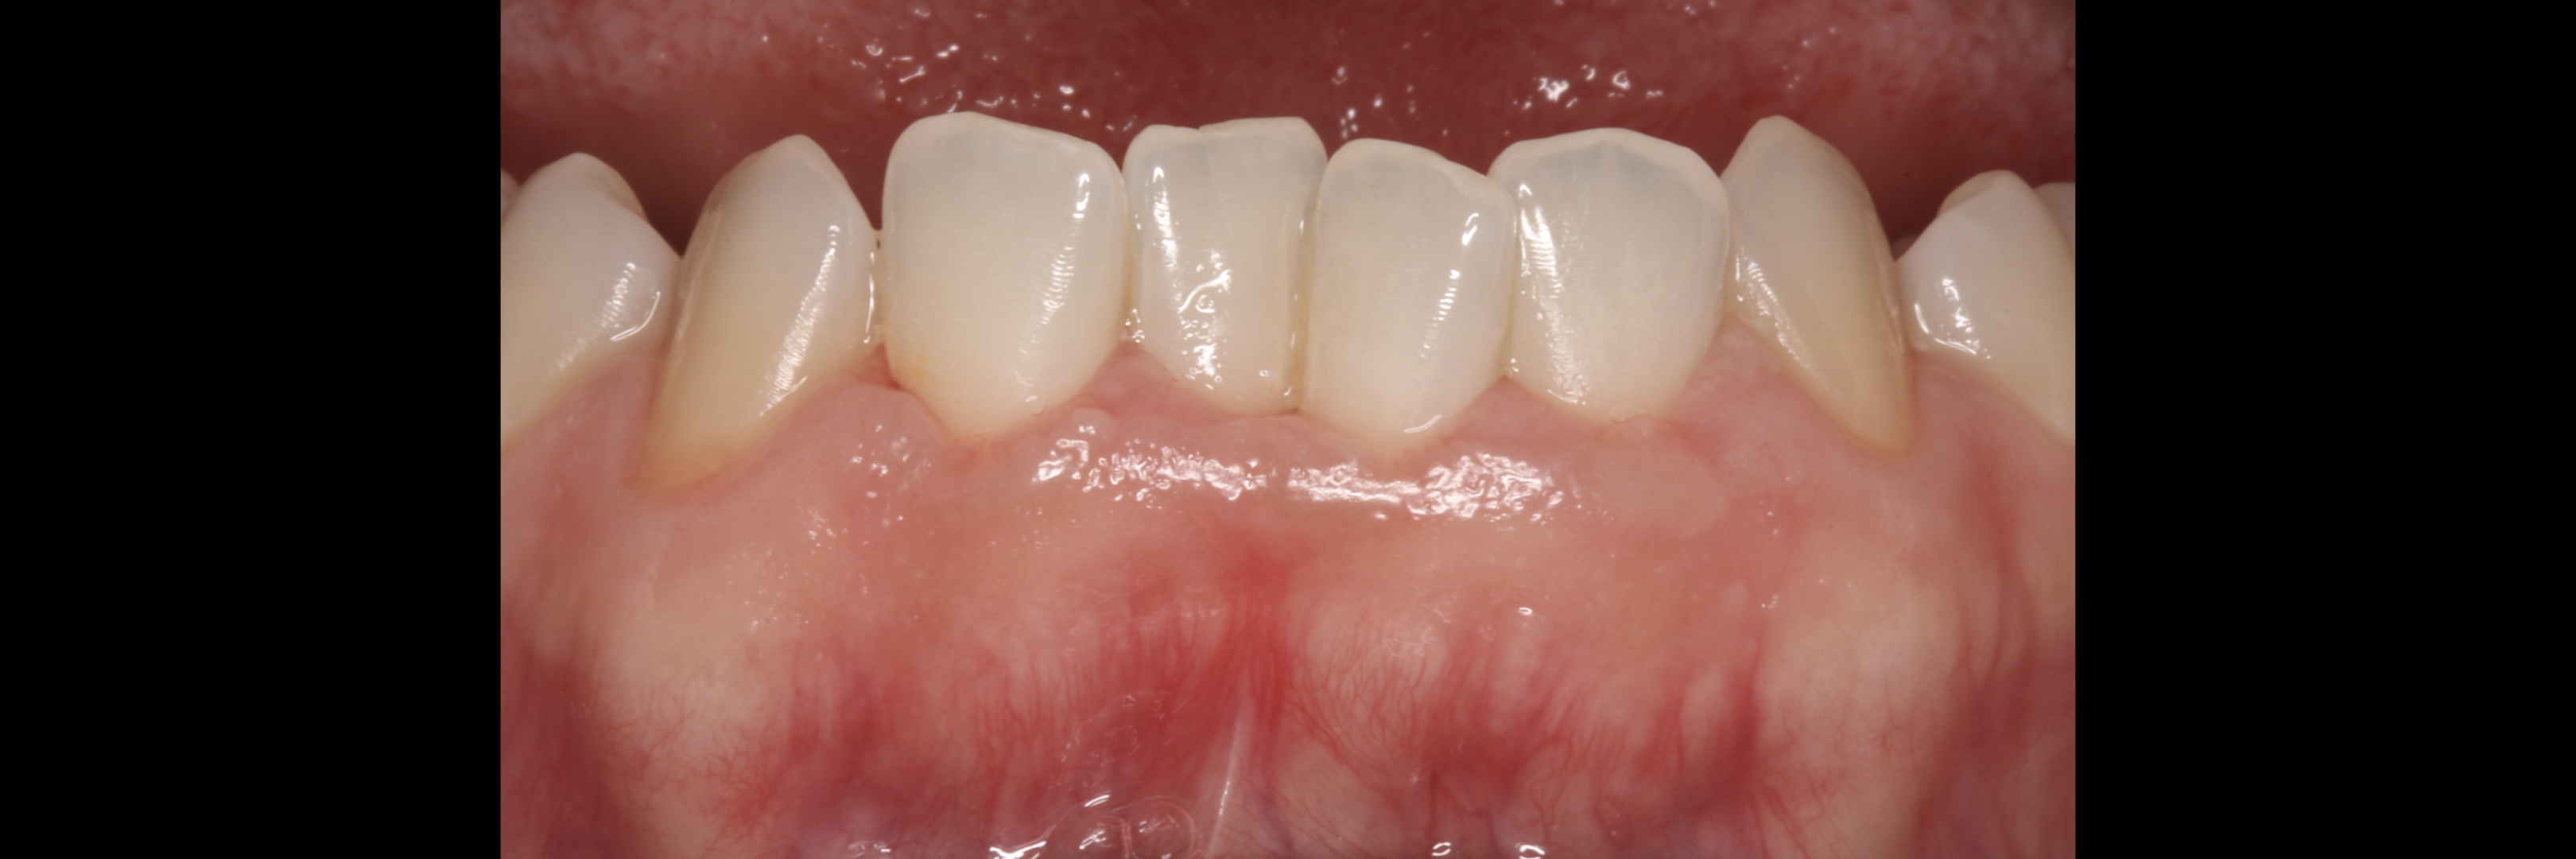

KERATINIZED gingiva includes

the free gingiva

(marginal gingiva & papillae)

and the attached gingiva extending from the gingival mar­gin to the mucogingival junction.

Also keratinized is the hard palate mucosa.

Generally we tend to forget about these 2 parameters, free and the attached gingiva are both essential parts of the keratinized gingiva.

This meaning that keratinized (load bearing capacity) is a mechanical characteristic that makes up for attached gingiva, providing it's immobility,  but also is of such importance as the thickness it provides around whatever perforates the epithelium, be it implants or teeth, being also keratinized (having load bearing capacity) at this location.

However free marginal gingiva is different in characteristics on its outer and inner surfaces: outer surface is keratinized;

inner surface is

non-keratinized, constituting part of the gingival sulcus.

The width of the keratinized gingiva may vary between 1 and 9mm.